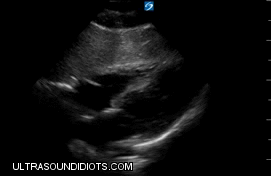

Echo Subcostal Exams